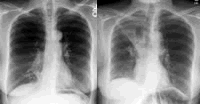

术前在家中由医务人员指导下进行呼吸康复训练4周。术前胸部X线片及高分辨率CT(HRCT)显示:重度肺气肿改变,双肺上叶病变明显,膈肌平坦,肋间隙增宽(图1左)。

术后24 h拍胸部X线片复查,见右上肺不张形成(图1右)。患者自觉气促较术前有改善。出院后继续术前药物治疗。1个月后复查肺功能:FEV1=0.97 L,FEV1%pred=52%,FVC=2.05 L,FVC%pred=86%,FEV1/FVC=47%,RV=2.13 L,RV%pred=106%,TLC=4.23 L,TLC%pred=89%,DLCO%=32%,6分钟步行距离445 m。动脉血气分析(FiO2=0.21):pH=7.36,PaO2=58 mmHg,PaCO2=40 mmHg,SaO2%=87%。自觉生活质量改善,可胜任一般家务劳动。